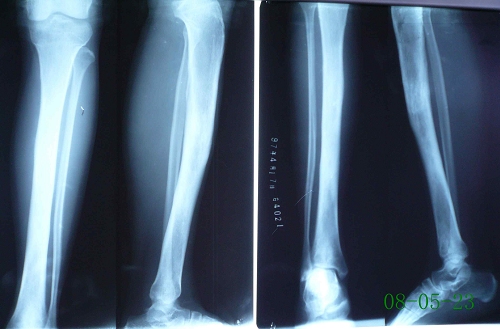

左胫骨慢性骨髓炎

图片尺寸1536x2048